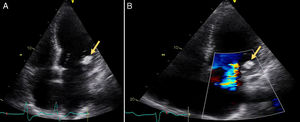

A 72-year old woman with a history of mechanical aortic prosthesis since 2010 and early infective prosthetic endocarditis (medical treatment) was hospitalized for acute heart failure in February 2015. Transesophageal echocardiography showed a severe paravalvular leak in the posterior portion of the aortic prosthesis (Figure 1A, arrow) and a pseudoaneurysm with fistulization to the left ventricle (LV) and aorta (Figure 1B, arrow), moderate mitral regurgitation and mild LV systolic dysfunction. Surgery was considered high risk and percutaneous closure of the paravalvular leak was attempted. The procedure was guided by fluoroscopy and transesophageal echocardiography. After confirming the stability of the device (Amplatzer® Vascular Plug II 12 mm/9 mm) and reduction of the paravalvular leak without functional compromise of the mechanical prosthesis (Figures 2A and 2B, arrow), the device was released. Minutes after deployment, the device migrated into the LV (Figure 3A, arrow and Supplementary data online, Movie S1). The device could not be retrieved (Figure 3B, arrow). Echocardiography images showed the device lodged beneath the posterior mitral leaflet, entrapped in the subvalvular mitral apparatus, with no significant compromise of mitral valve function (Figures 4A, arrow and 4B, arrow and Supplementary data online, Movie S2). Follow-up echocardiographies showed the device still in the same position. The patient died of sepsis due to a Clostridium difficile infection 58 days after admission (one month after the procedure). This case illustrates a rare and dramatic complication of percutaneous leak closure, but without significant hemodynamic impact on mitral valve and LV function.